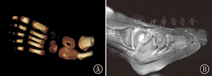

术后病理结果显示7个病种:感染性疾病6例[慢性或亚急性骨髓炎4例(典型病例见图1、图2),结核2例(典型病例见图3、图4)],骨血管瘤2例(典型病例见图5、图6),骨囊肿、骨软骨母细胞瘤、骨纤维结构不良、骨样骨瘤各1例。12例患儿的一般资料、实验室检查、影像学特点及病理诊断结果见表1。

儿童距骨骨质破坏病理类型较多,病理类型的多样性对影像学定性诊断、鉴别诊断提出了挑战,术后病理学检查仍是获得正确诊断的较好选择。本组12例中,8例术前未能得到正确诊断。2岁以内的患儿踝关节肿痛早期多被误诊为蚊虫咬伤所致血管神经性水肿。>2岁的儿童踝关节肿痛早期多数误诊为外伤。实验室检查往往对距骨骨质破坏患儿诊断的意义并不大,尽管恶性骨质破坏多有贫血,ESR轻度增高,但感染性疾病及结核往往也伴有ESR增高。术后病理诊断以感染性(慢性或亚急性骨髓炎4例和结核2例)和骨肿瘤样病变(骨血管瘤2例,骨囊肿1例,骨软骨母细胞瘤1例,骨纤维结构不良1例)多见。分析本组病例术后的病理结果,发现儿童距骨骨质破坏以≤2岁的患儿最为多见(8例,约占67%)。≤2岁患儿的距骨骨质破坏多为感染性病变(慢性或亚急性骨髓炎4例,结核2例),>2岁患儿的距骨骨质破坏多为肿瘤样病变(骨血管瘤2例,骨囊肿、骨软骨母细胞瘤、骨纤维结构不良各1例),未见恶性肿瘤发生。儿童距骨的恶性肿瘤非常罕见,文献报道仅见2例报道[5,6]。推测儿童距骨骨质破坏可能与距骨位置低,负重大,易损伤,加之周围缺少丰富的肌肉覆盖易被侵袭而发病有关。同时距骨是负重骨,当发生囊样病变时易发生病理性骨折。